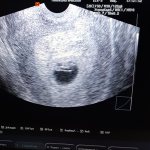

18.12.20 сходила на первое УЗИ своего 3 ребёнка,всё идёт хорошо,по срокам на тот момент было 7 недель и 3 дня 👶🍼🥰